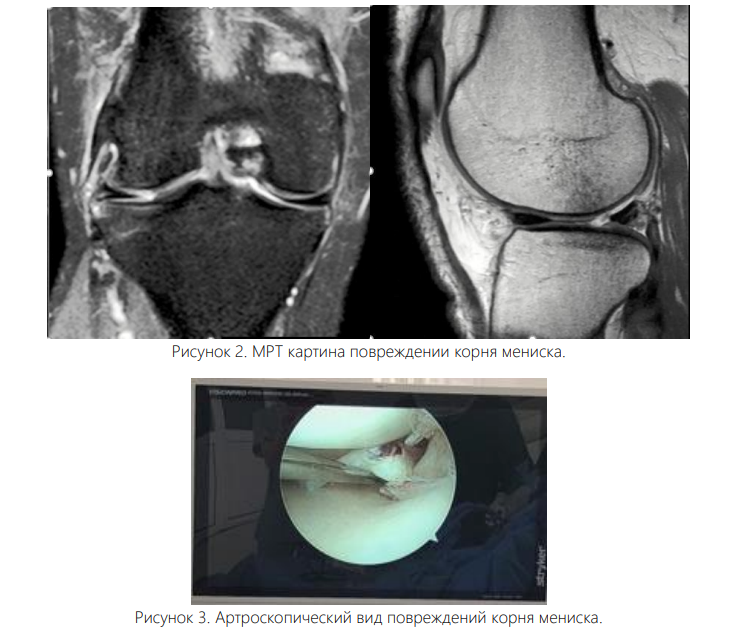

МРТ по-прежнему является золотым стандартом для выявления РКМ с помощью визуализации, причем предпочтительным методом являются Т-2-взвешенные изображения [7, 15].

Несколько классических находок могут помочь выявить наличие патологии корня мениска. К ним относятся «признак усечения» (наличие вертикального линейного дефекта у корня мениска на коронарных сериях, часто с выпячиванием мениска), «признак призрака» (отсутствие нормального сигнала мениска на сагиттальных сериях) и «радиальный разрыв» (высокий сигнал, линейные интенсивности, появляющиеся перпендикулярно корню мениска на аксиальных сериях) [15]. Рисунок 2. МРТ картина повреждении корня мениска.

Несмотря на эти признаки, было отмечено, что МРТ может не обнаружить разрывы. Бхатиа и соавторы сообщили, что до 1/3 медиальных РКМ могут быть пропущены при визуализации [7].

Аналогичным образом, Krych и коллеги дополнительно продемонстрировали, что предоперационная МРТ, прочитанная радиологами, прошедшими обучение в области опорно-двигательного аппарата, обнаружила только 33% латеральных РКМ, и только 50% известных разрывов были «явно заметны» на изображениях, повторно проанализированных после операции [12]. Таким образом, хотя МРТ остается наиболее надежным нехирургическим методом выявления РКМ, хирурги должны осознавать возможность пропущенных диагнозов и тщательно исследовать задний корень латерального мениска во время артроскопии. Классификация. Классификация травм на основе морфологии разрыва позволяет улучшить диагностику и лечение. Система классификации, описанная LaPrade et al. [11], остается действующим стандартом. Тип 1 (7 %) — частичный, механически стабильный разрыв. Тип 2 (68%) — полные радиальные разрывы, происходящие в пределах 9 мм от костного прикрепления корня. Тип 3 (6%) — полное отслоение корня с сопутствующим разрывом в виде ручки ведра. Тип 4 (10%) — полное отслоение корня на фоне сложных косых разрывов. Тип 5 (9%) — костные отрывные переломы в месте прикрепления корня [15, 16].